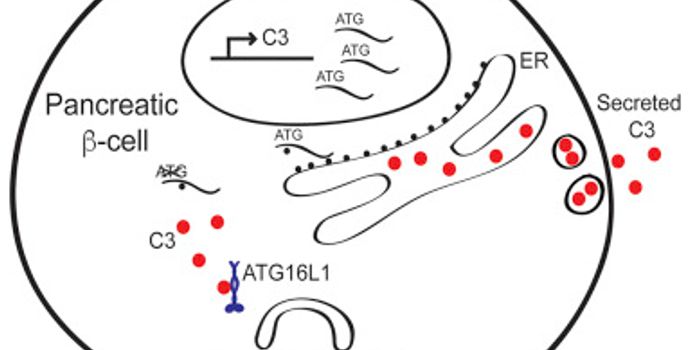

FEB 06, 2017ImmunologyThe recent discovery of not just one, but multiple genes that fail to protect the gastrointestinal (GI) tract from infla ...